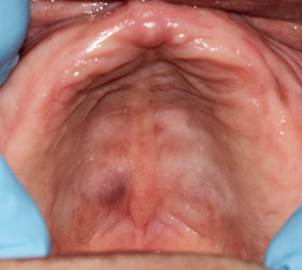

Reporte de Caso 1: Paciente de sexo femenino, 69 años, consulta por un aumento de volumen asintomático en paladar, de 10 años de evolución. La paciente presentaba hipertensión arterial e hipotiroidismo en tratamiento. Además, era desdentada total superior y portadora de prótesis removible. Al examen intraoral, presentaba tumoración de forma ovalada en paladar duro, de 12x7 mm, cubierto por mucosa normal, superficie lisa, límites definidos, base sésil y consistencia renitente (Figura 1). Se realizó biopsia con hipótesis clínica de adenoma pleomorfo.

Al examen intraoral era desdentada total superior y parcial inferior, con múltiples lesiones cariosas y portadora de prótesis. A nivel palatino presentaba nódulo en límite de paladar duro-blando hacia la derecha, próximo a línea media, redondeado, azul, superficie lisa, fluctuante, 5 mm de diámetro, indoloro, con un tiempo de evolución desconocido (Figura 3). Se realizó ecografía de paladar por sospecha de malformación vascular, que concluye lesión de aspecto quístico en el sector posterior derecho de paladar duro, con contenido denso (Figura 4).